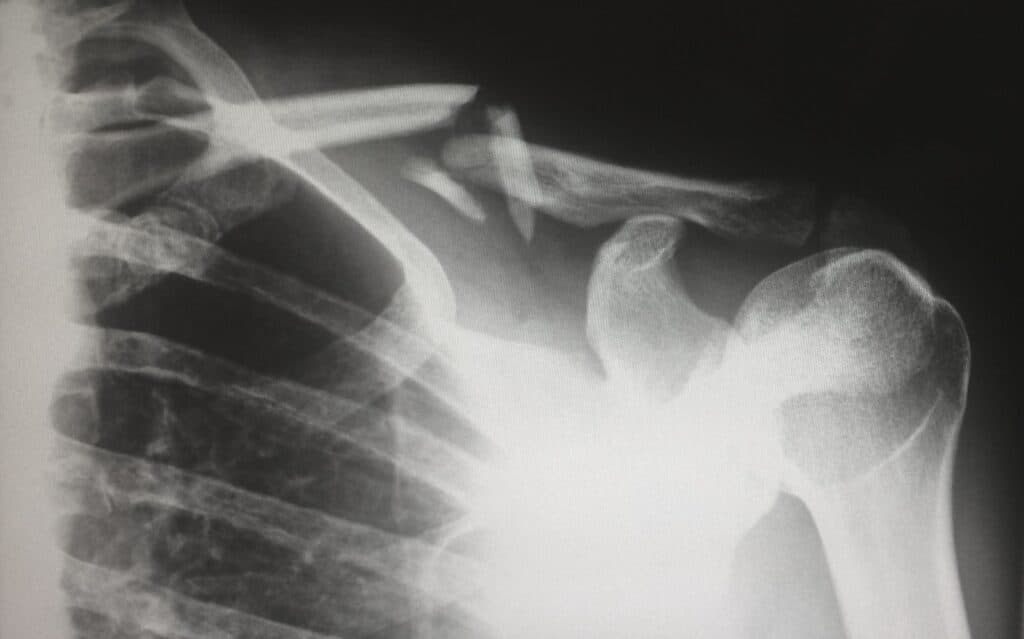

Sempre que lá entro vou a reclamar da vida. Ora traz um pé amassado, um braço inchado ou qualquer outra marca de guerra resultante de futeboladas disputadas com temperaturas negativas. Certo como o destino, vou ter de passar pelo raio-x, e isso num hospital que parece um estaleiro significa que vou andar a fazer os 800 metros obstáculos.